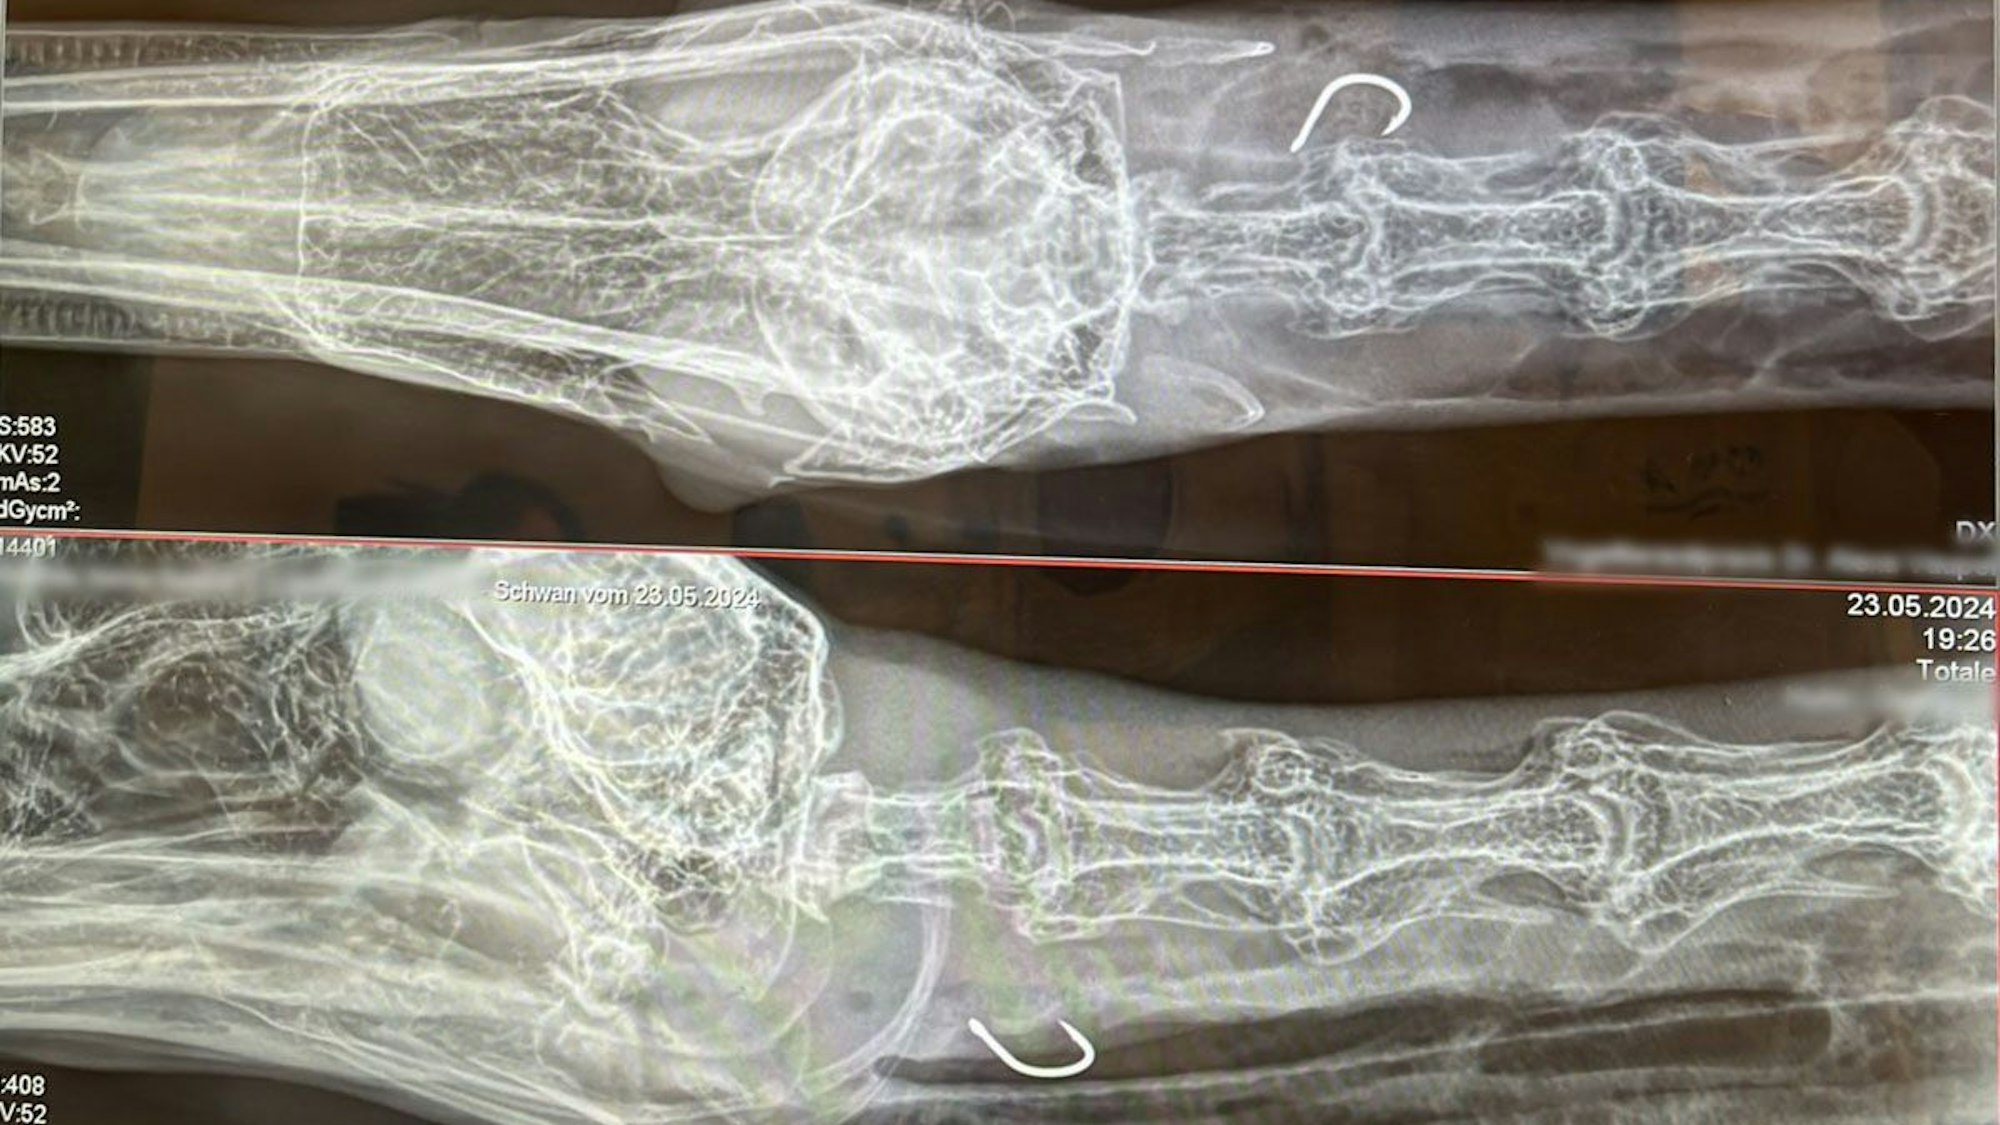

Auf den Röntgenaufnahmen ist der Angelhaken zu sehen, welcher in der Speiseröhre des Schwans feststeckte.

Bröckling konnte den geschwächten Schwan mit einem Sprung ins Wasser einfangen und ihn an Land bringen. Gemeinsam mit Scherping brachte er das Tier anschließend zu einem Tierarzt. Dieser stellte fest, dass der Angelhaken mit Widerhaken in der Speiseröhre des Vogels feststeckte. Trotz Not-OP starb der Schwan noch in derselben Nacht.